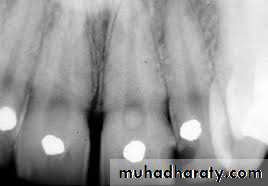

Denticles/pulp stones. These are usually seen in pulp chamber.

1. According to location:•Free

• Embedded

• Attached

2. According to structure:

True denticles: It is composed of dentin formed from detached odontoblasts or fragments of Hertwig’s enamel root sheath which stimulate an undifferentiated cells to assume dentinoblastic activity.False denticles: Here degenerated tissue structures act as nidus for deposition of concentric layers of calcified tissues.